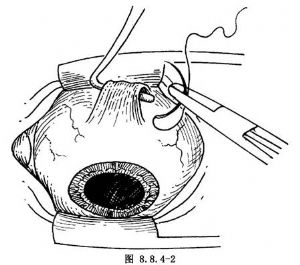

多采用角膜緣切口(圖8.8.4-1A、B),也可距角膜緣4~6mm切口。用剪刀剪開結膜及球筋膜後,貼鞏膜表面鈍性分離。鞏膜暴露多采用眼外肌牽引線法。先以彎剪刀分離直肌止端兩側及表麪筋膜組織。用斜視鉤遊離並鉤起直肌,1號絲線穿過直肌下(圖8.8.4-2)。如暴露1個象限鞏膜,牽拉該象限兩側直肌牽引線,配合開瞼鉤即可(圖8.8.4-3)。如暴露的鞏膜部位非常靠後,或暴露直肌下的鞏膜,有時要暫時切斷某條直肌。斷肌肉前,先預置肌肉縫線(圖8.8.4-4)。